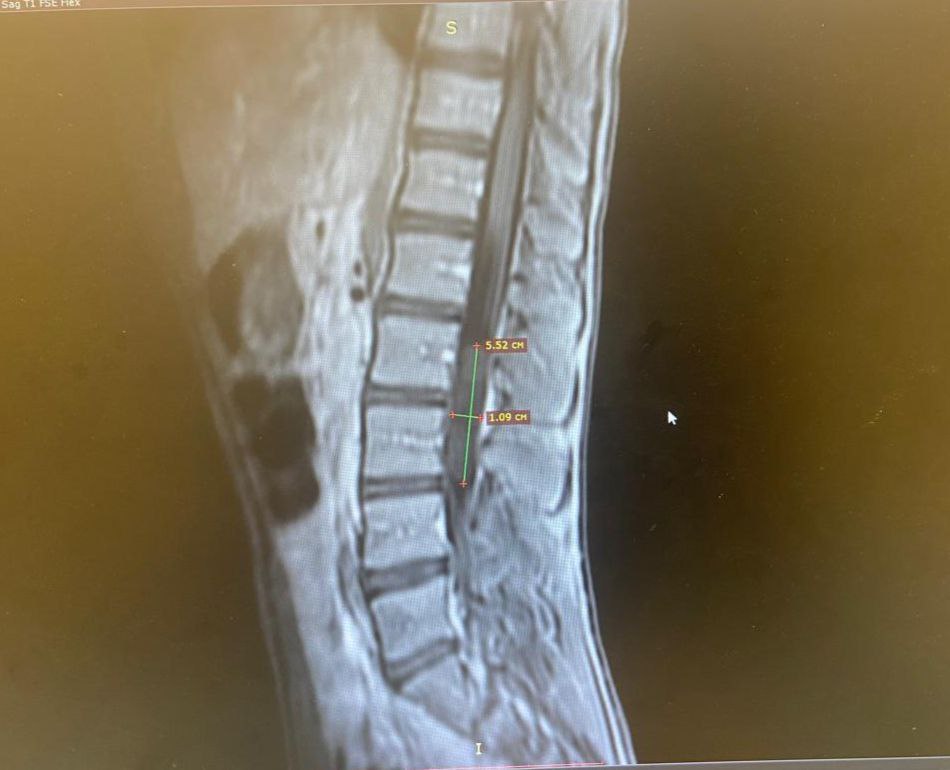

На снимке МРТ врачи обнаружили редкое доброкачественное образование – холестеатому. Она распространилась на два поясничных позвонка. Опухоль полностью перекрывала просвет спинномозгового канала, сдавливая корешки спинного мозга и вызывая болевой синдром у ребенка.